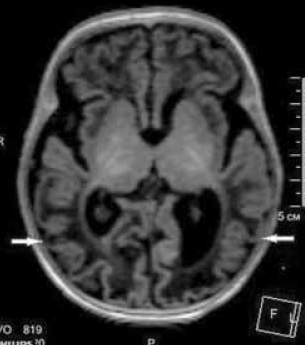

Выполнена магнитно-резонансная томография (МРТ) головного мозга через 3 недели после первого эпизода судорожных приступов (возраст ребенка на момент проведения исследования 6 недель) на аппарате Philips Ingenia1, 5 T. Получены Т1- Т2-взвешенные изображения, FLAIR-, DWI-изображения. На изображениях МРТ отмечаются зоны диффузных изменений МР-сигнала в теменно-затылочно-височных долях (рис. 6–8) без изменения архитектоники борозд и извилин. На представленных изображениях МРТ в аксиальной плоскости выявляются диффузные атрофические изменения коры головного мозга в затылочных долях, где толщина коры не превышает 1 мм, в сравнении с неизмененной корой в других отделах (рис. 6). На рис. 7 представлены изменения МР-сигнала (FLAIR) от измененной коры в теменно-затылочно-височных долях, без изменения архитектоники извилин. На DWI-картах сохраняются диффузные изменения МР-сигнала от структур затылочных долей, а также более отчетливо видны изменения сигнала от колена мозолистого тела (наконечник стрелки) (рис. 8).

Рис. 6. МРТ головного мозга ребенка в возрасте 6 недель с неонатальной гипогликемической энцефалопатией. Аксиальная плоскость, Т1 ВИ. Стрелками указаны изменения толщины коры головного мозга затылочных долей